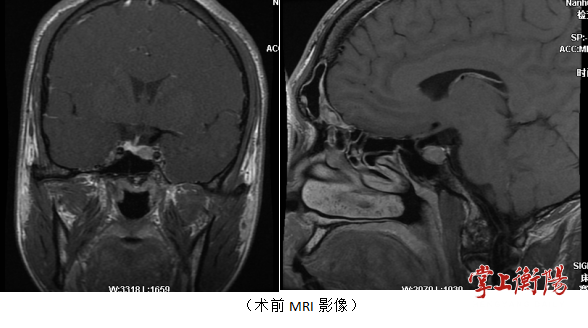

患者入院后,南华医院神经外科积极为患者完善垂体磁共振(MRI)及相关激素检查,考虑垂体生长激素腺瘤可能,经由南华医院神经外科颅底肿瘤亚专科治疗组成员讨论后,建议患者进行手术治疗。经过仔细的术前讨论及准备后,南华医院神经外科颅底肿瘤亚专科团队成功为患者剜除了垂体腺瘤,术后第二天患者便下床自主活动,目前患者已无明显不适,顺利出院。